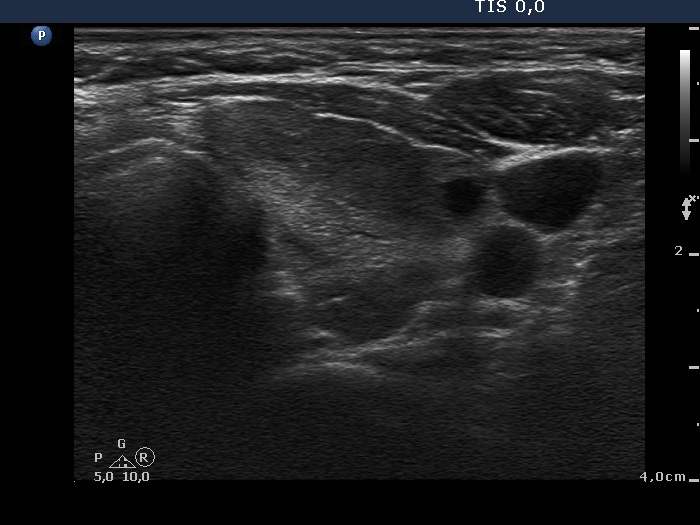

Follow-up examination 12 months later (second row):

Clinical presentation: The patient did not undergo radioiodine therapy. She was well and euthyroid on thyrostatic therapy in the previous year.

Palpation: Both thyroids were enlarged and moderately firm.

Result of blood test: subclinical hyperthyroidism on daily 10 mg methimazole (TSH undetectable, FT4 13.4 pM/L, FT3 5.05 pM/L).

Ultrasonography: The extent of hypoechogenic areas have decreased, otherwise the pattern was unchanged.We suggested again a repeat radioiodine therapy.